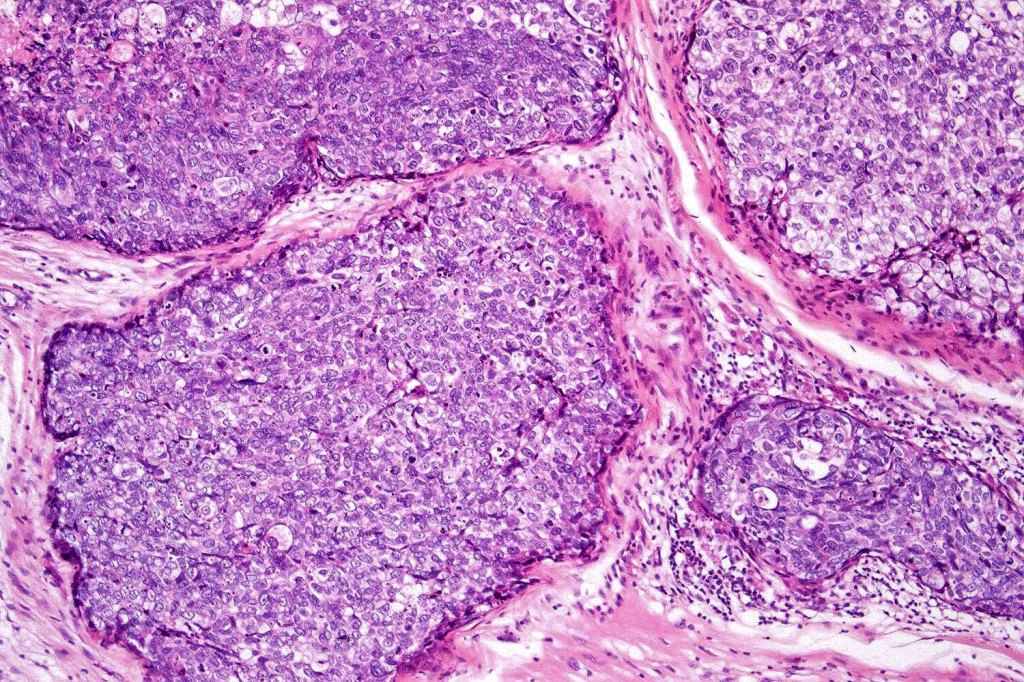

•Well differentiated lobular growth pattern though to a poorly differentiated tumor often showing a diffuse, infiltrating border which may extend into the subcutaneous fat

•Peripheral palisading with retraction artifact and mucin deposition as seen in basal cell carcinoma is not present

•Comedo type necrosis commonly present

•Tumors are composed of an admixture of darkly staining basaloid cells with hyperchromatic or vesicular nuclei and more obvious sebaceous cells with eosinophilic, bubbly, multivacuolated cytoplasm frequently indenting the nucleus (scalloped)

•Often mitoses are numerous and abnormal forms evident